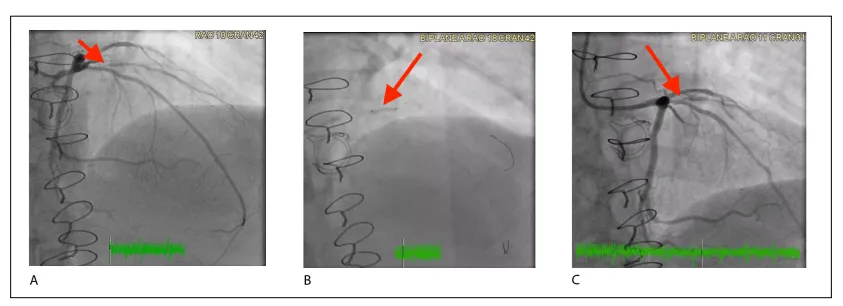

关于DCB治疗de novo小血管CAD疗效报告的不一致,以及多个试验结果的不一致,可能归因于不同DCB技术之间缺乏类效应,以及手术技术的差异,特别是病变准备不充分。例如,PICCOLETO(药物洗脱球囊治疗小冠状动脉血管疾病疗效)研究中相互矛盾的发现可以部分解释为大约75%的入组患者存在次优的病变预扩张。表2提供了DCB在de novo小血管冠状动脉疾病中的主要RCTs总结。图6和图7说明了我们成功应用AGENT DCB治疗de novo小血管CAD的案例。

图7 冠状动脉造影图像展示使用药物涂层球囊(DCB)治疗累及第一对角支开口处、狭窄程度达90%的原发小血管病变。(A) 术前图像显示第一对角支开口处存在90%狭窄。(B) 术中释放2.5 × 12 mm的AGENT药物涂层球囊,以4个大气压扩张60秒。(C) 术后图像显示DCB干预后狭窄程度改善至30%,血管通畅性显著提升。